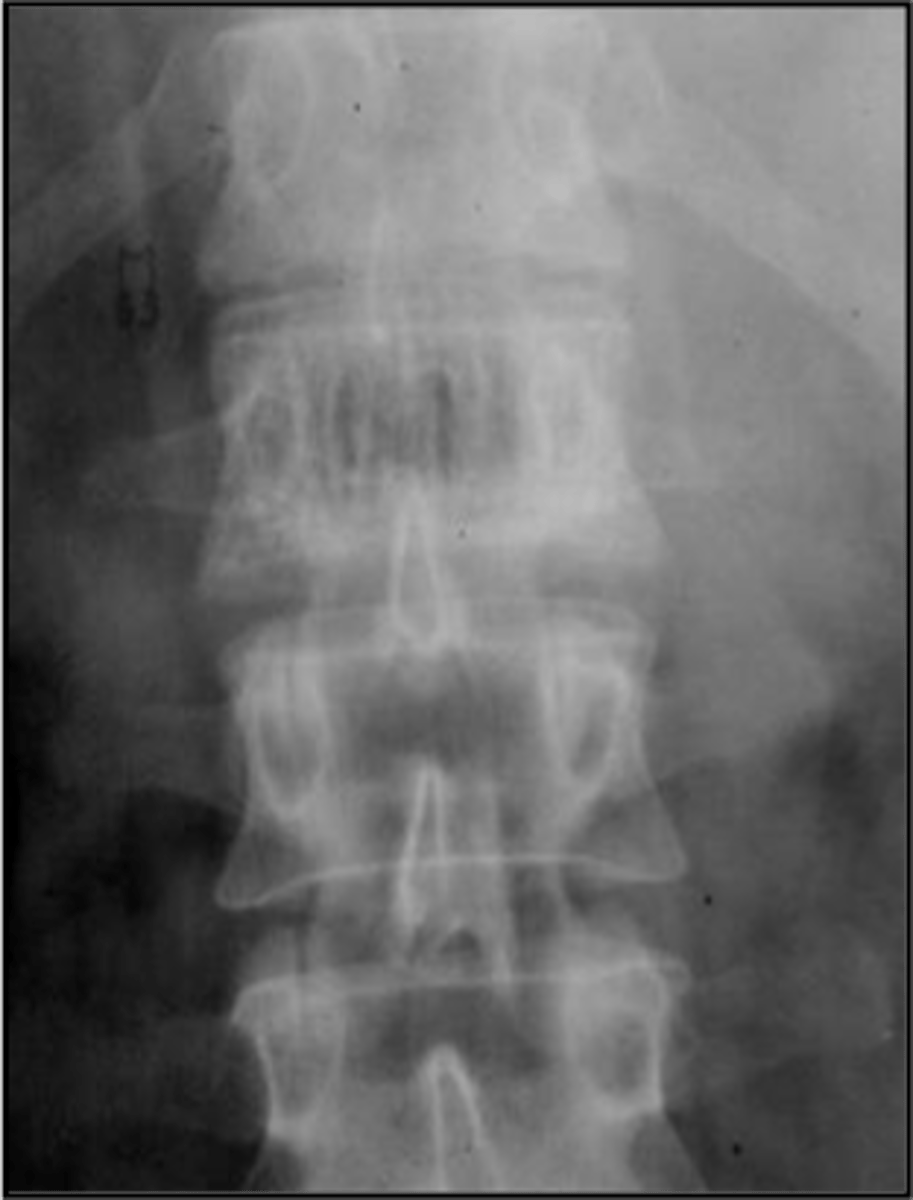

- Bone island

- Kidney stone*

22 y.o. male with L/S pain, post motor vehicle accident

- Differential diagnosis?

<p>22 y.o. male with L/S pain, post motor vehicle accident</p><p>- Differential diagnosis?</p>